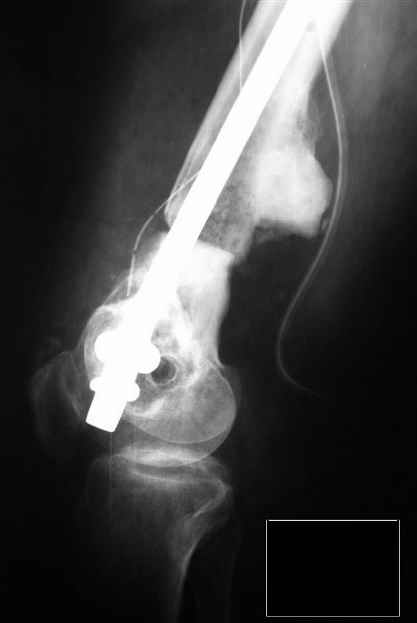

Действительно, выстоит стержень избыточно, суставную поверхность надколенника будет травмировать. А в чем проблема была, почему не удалось его глубже ввести? У конструкции ChM есть "ступенька" на уровне соединения ретроградного стержня с кондуктором, которая способствует неполному погружению, но не в такой степени.

На интраоперационных снимках мы видили неполное погружение гвоздя, поэтому добили и завершили на этом. Думаем, что нам помешала ретракция собственной связки надколенника, здорово осложнившая обзор, особенно когда она натянулась после воостановления длины сегмента.